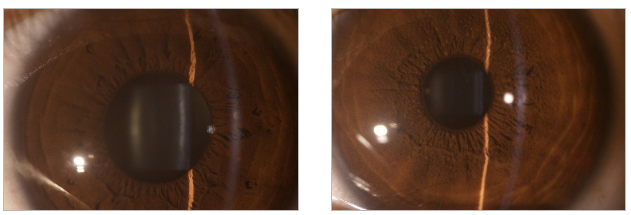

台湾miis赫罗斯ILS 100型医用检查镜/手持裂隙灯临床图库: